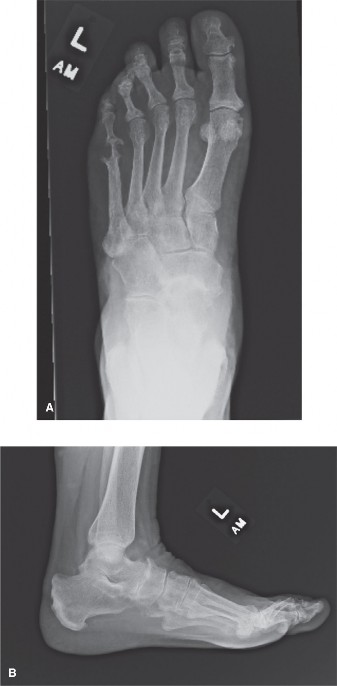

A 47-year old woman presents with 2 years of atraumatic hindfoot pain. She has noticed the gradual onset of p…